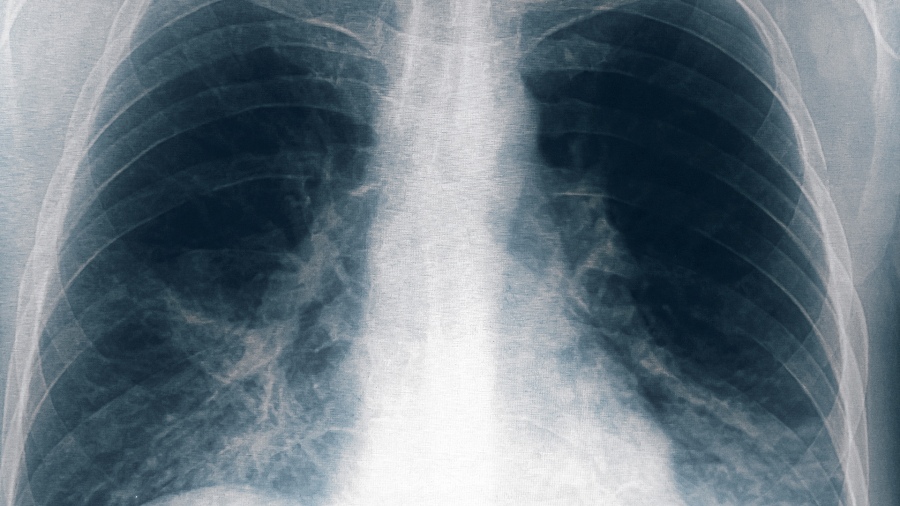

Un paciente “vinculado al conglomerado de casos de neumonía” bilateral registrados en Tucumán murió este domingo, por lo que suman cinco las víctimas fatales por esta causa, informó el Ministerio de Salud Pública provincial.

Hasta el momento se identificaron once personas afectadas por neumonía bilateral causada por Legionella, en la clínica privada Luz Médica, de las cuales cinco fallecieron.

Los primeros seis casos registrados correspondieron a cinco trabajadores de la salud y a una paciente que estaba internada en el servicio de terapia intensiva de un sanatorio privado de la ciudad de San Miguel de Tucumán, quienes iniciaron síntomas entre el 18 y el 22 de agosto, presentando fiebre, mialgia, dolor abdominal y disnea.